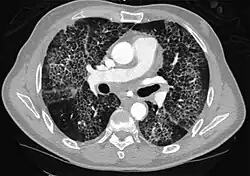

High-Resolution CT image in a patient with Pneumocystis pneumonia infection showing ground-glass opacities.

Inflammation and fibrosis can also cause diffuse GGOs. Pneumocystis pneumonia, an infection typically seen in immunocompromised (e.g. patients with AIDS) or immunosuppressed individuals, is a classic cause of diffuse GGOs. Many viral pneumonias and idiopathic interstitial pneumonias can also lead to a diffuse GGO pattern. Radiation pneumonitis, a side effect of pulmonary radiation therapy, can lead to pulmonary fibrosis and diffuse GGOs.[6]